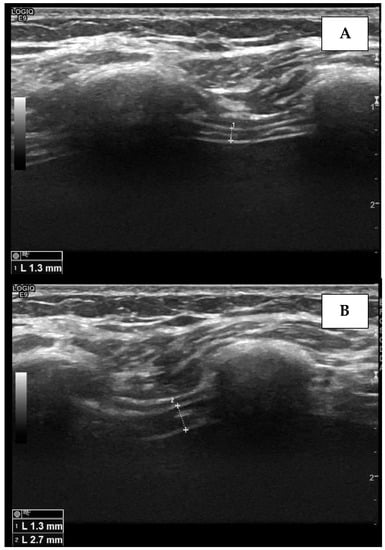

4.2. The Apposition Zone Approach